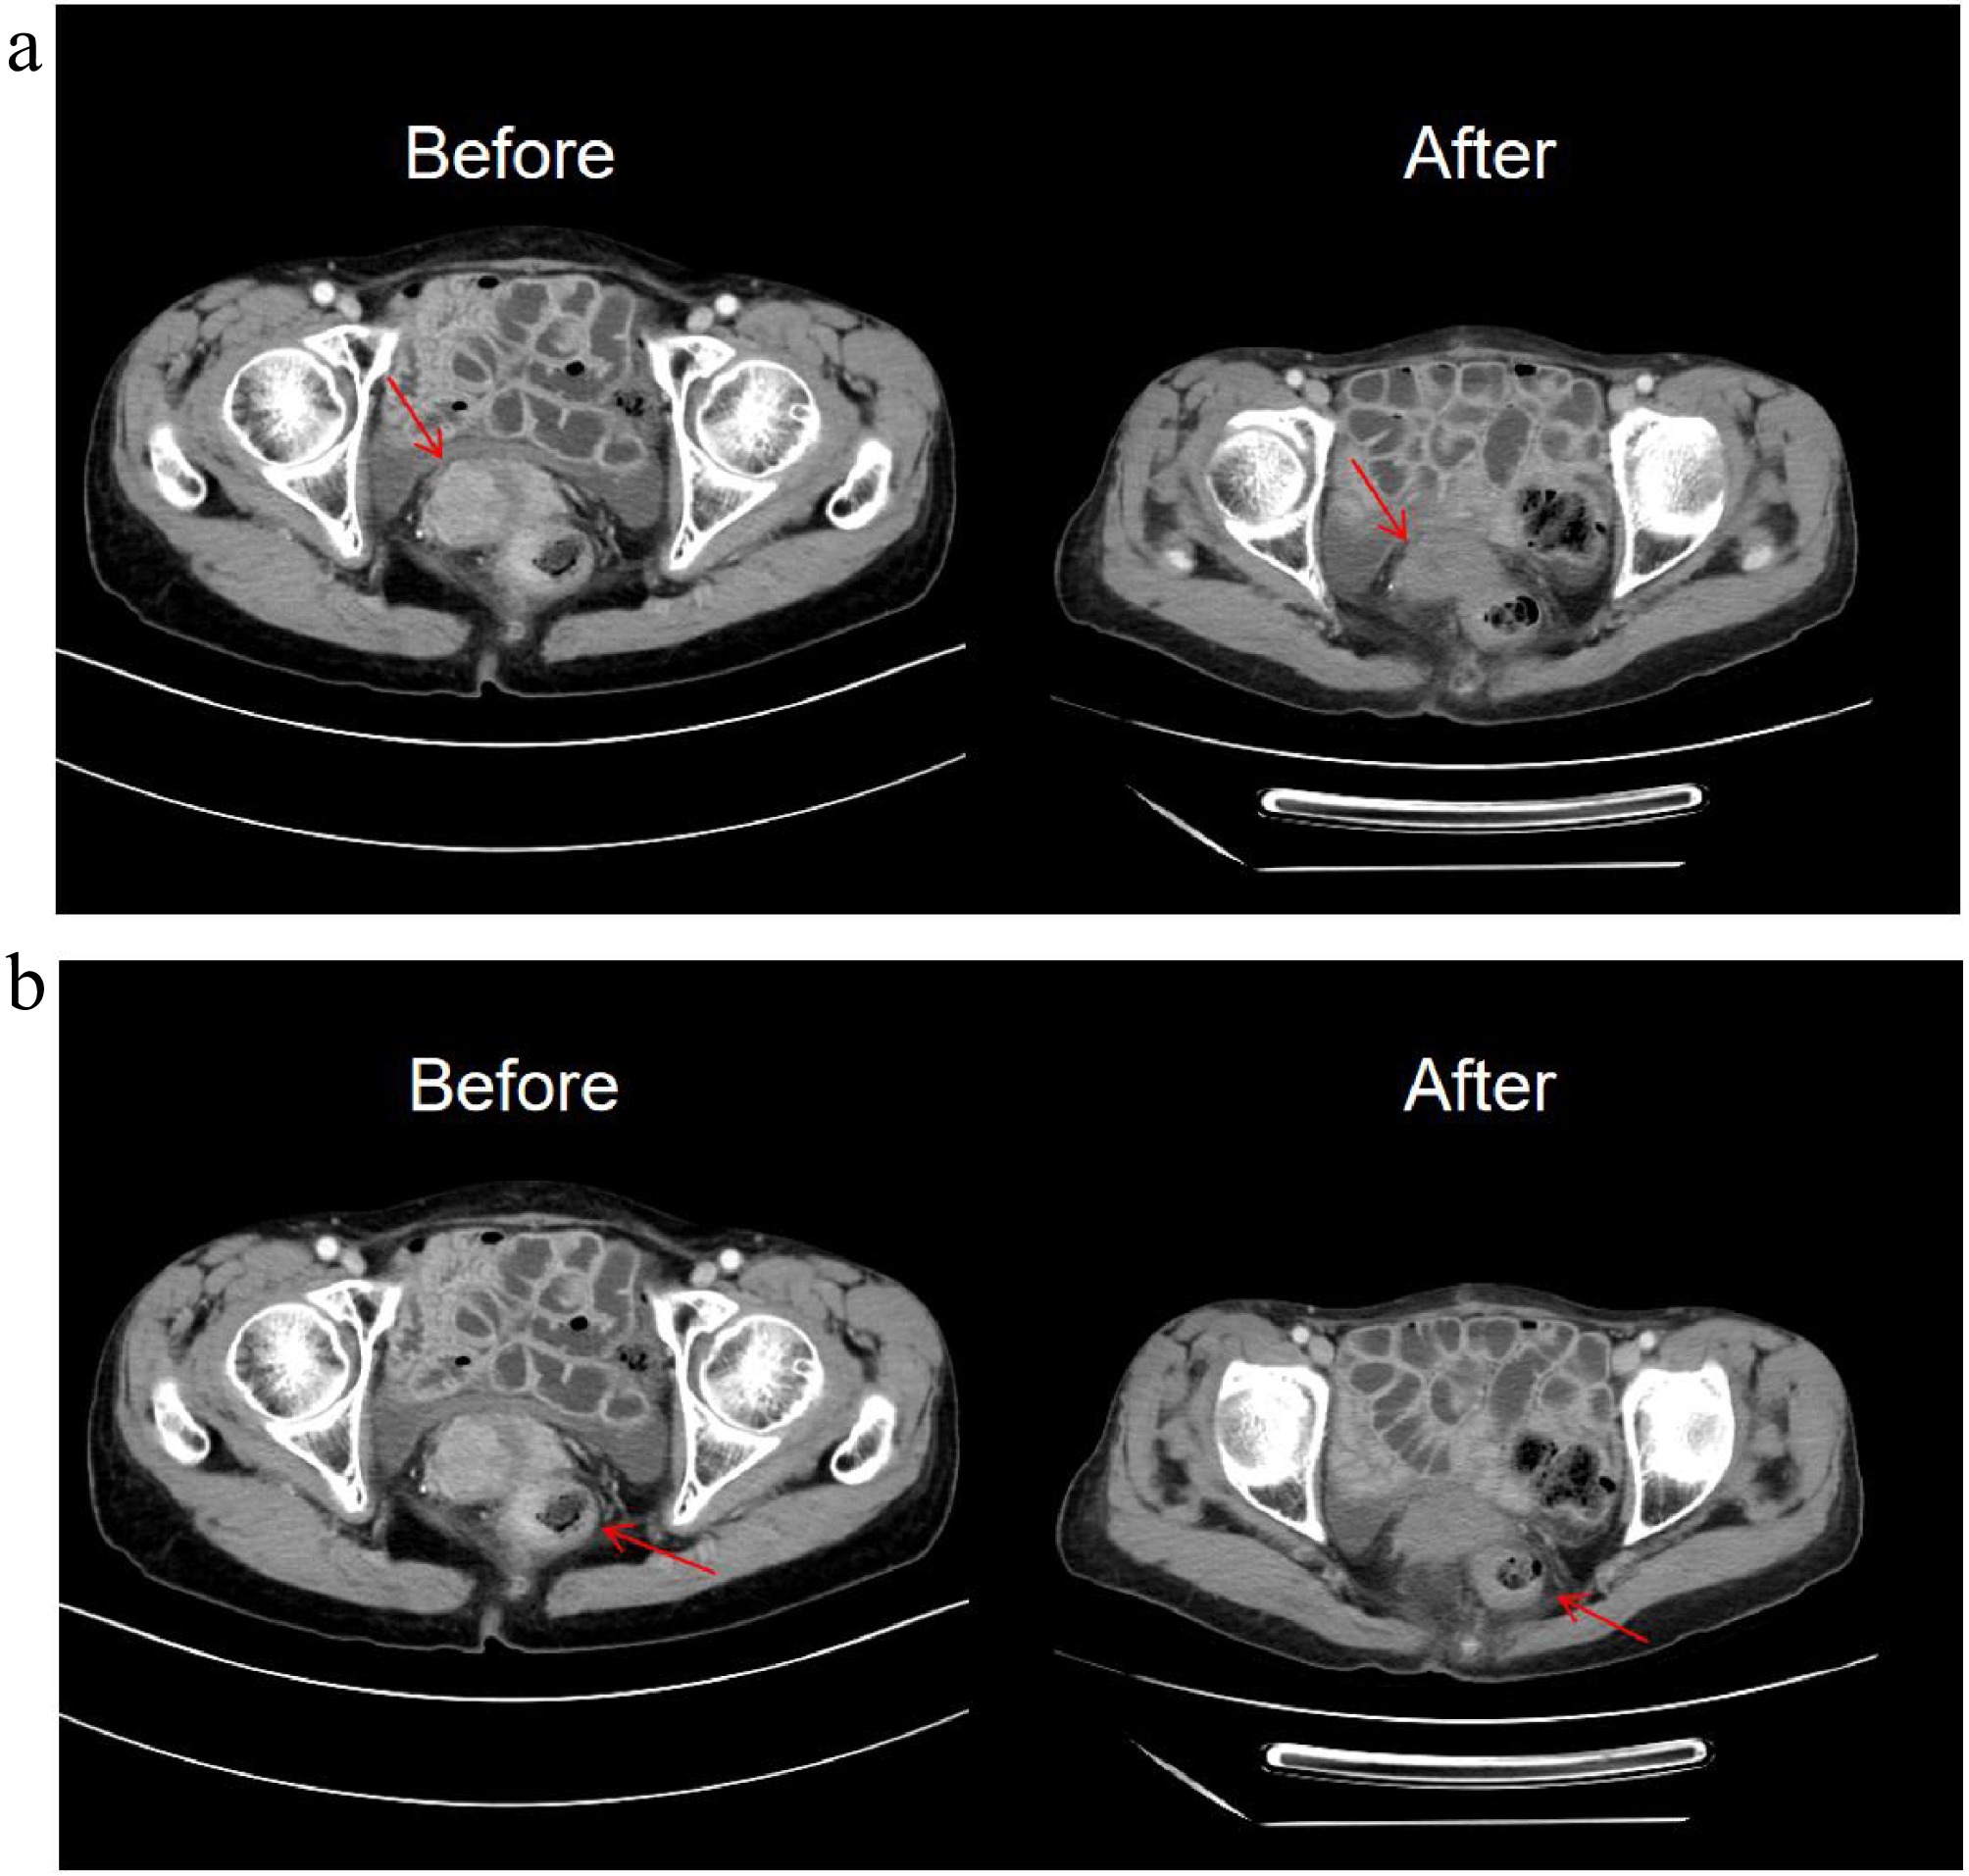

Figure 2.

Patient CT and MRI image. (a) Patient 2024.9.28 CT image. (b)–(d) Patient 2024.10.24 MRI image.

This patient the underwent chemotherapy with oxaliplatin + capecitabine (CAPOX) on October 26, 2024. CSCO Gastric Cancer Guidelines (2024): Chemotherapy-immunotherapy (chemotherapy + anti-PD-1/PD-L1) is recommended as the first-line treatment for unresectable advanced gastric cancer, regardless of PD-L1 expression status (including CPS < 5), and the patient lacks alternative targeted therapy (HER2-negative). Based on the CPS, sintilimab (anti-PD-1) was added from November 25, 2024, to April 15, 2025, completing six cycles of CAPOX plus sintilimab. During therapy, the patient developed grade 3 thrombocytopenia (occurred after cycle 6, 2025-04), and grade 2 leukopenia (occurred after cycle 2, 2024-12). Recombinant human thrombopoietin (rhTPO) and granulocyte colony-stimulating factor (G-CSF) were retrospectively administered for symptomatic treatment. The patient completed all six cycles as planned, and no serious or persistent adverse events occurred. Tumor marker CA72-4 monitoring demonstrated a declining trend, eventually normalizing (Supplementary Fig. S1). Follow-up CT imaging revealed a reduction in the cervical and rectal masses, and this patient showed alleviation of intestinal obstruction symptoms. The therapeutic response was evaluated as partial response (PR) per RECIST 1.1 criteria (Fig. 4).